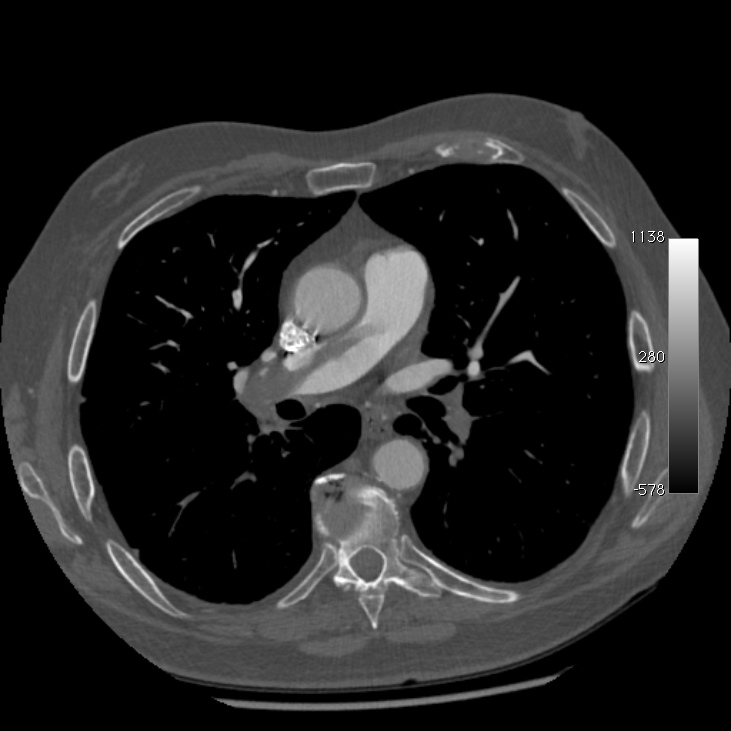

En coupe native :

Et après reconstruction pour expliquer la coupe échographique suprasternale (merci OsiriX) :

Grace à OsiriX et à Aurélie (respectivement déesse et fée du DICOM), voici un petit film de l’angisocanner, mais en coupe sagittales, on entre par l’épaule droite (le générique est un peu long et n’est pas sans évoquer celui de « Star Wars »), le voyage se poursuit par l’énorme thrombus droit, puis la crosse aortique :